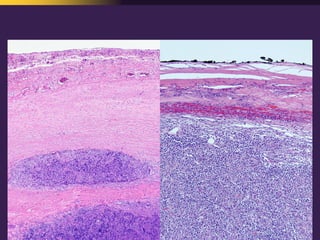

This document discusses mediastinal pathology using a compartmental approach. It describes the anatomy of the mediastinum and divides it into anterior, middle, and posterior compartments. Each compartment contains different structures and has a characteristic distribution of lesions. For example, 50% of lesions occur in the anterior compartment, which contains the thymus. The thymus is the most common site of lesions in the anterior compartment. Thymomas are the most common epithelial tumors of the thymus and mediastinum.